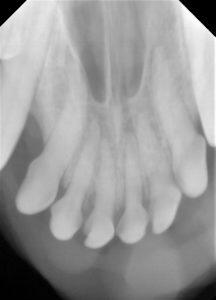

5.歯科レントゲンで歯と骨の状態を確認して

6.すべてのレントゲンを撮ってから、治療計画を立て